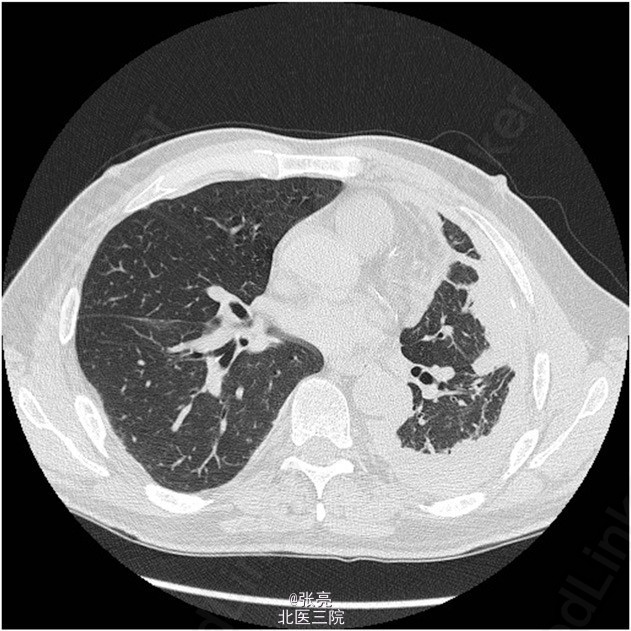

胸片提示左侧胸腔积液。CT扫描显示弥漫性胸膜增厚和肺胸膜大块侵入左肺。